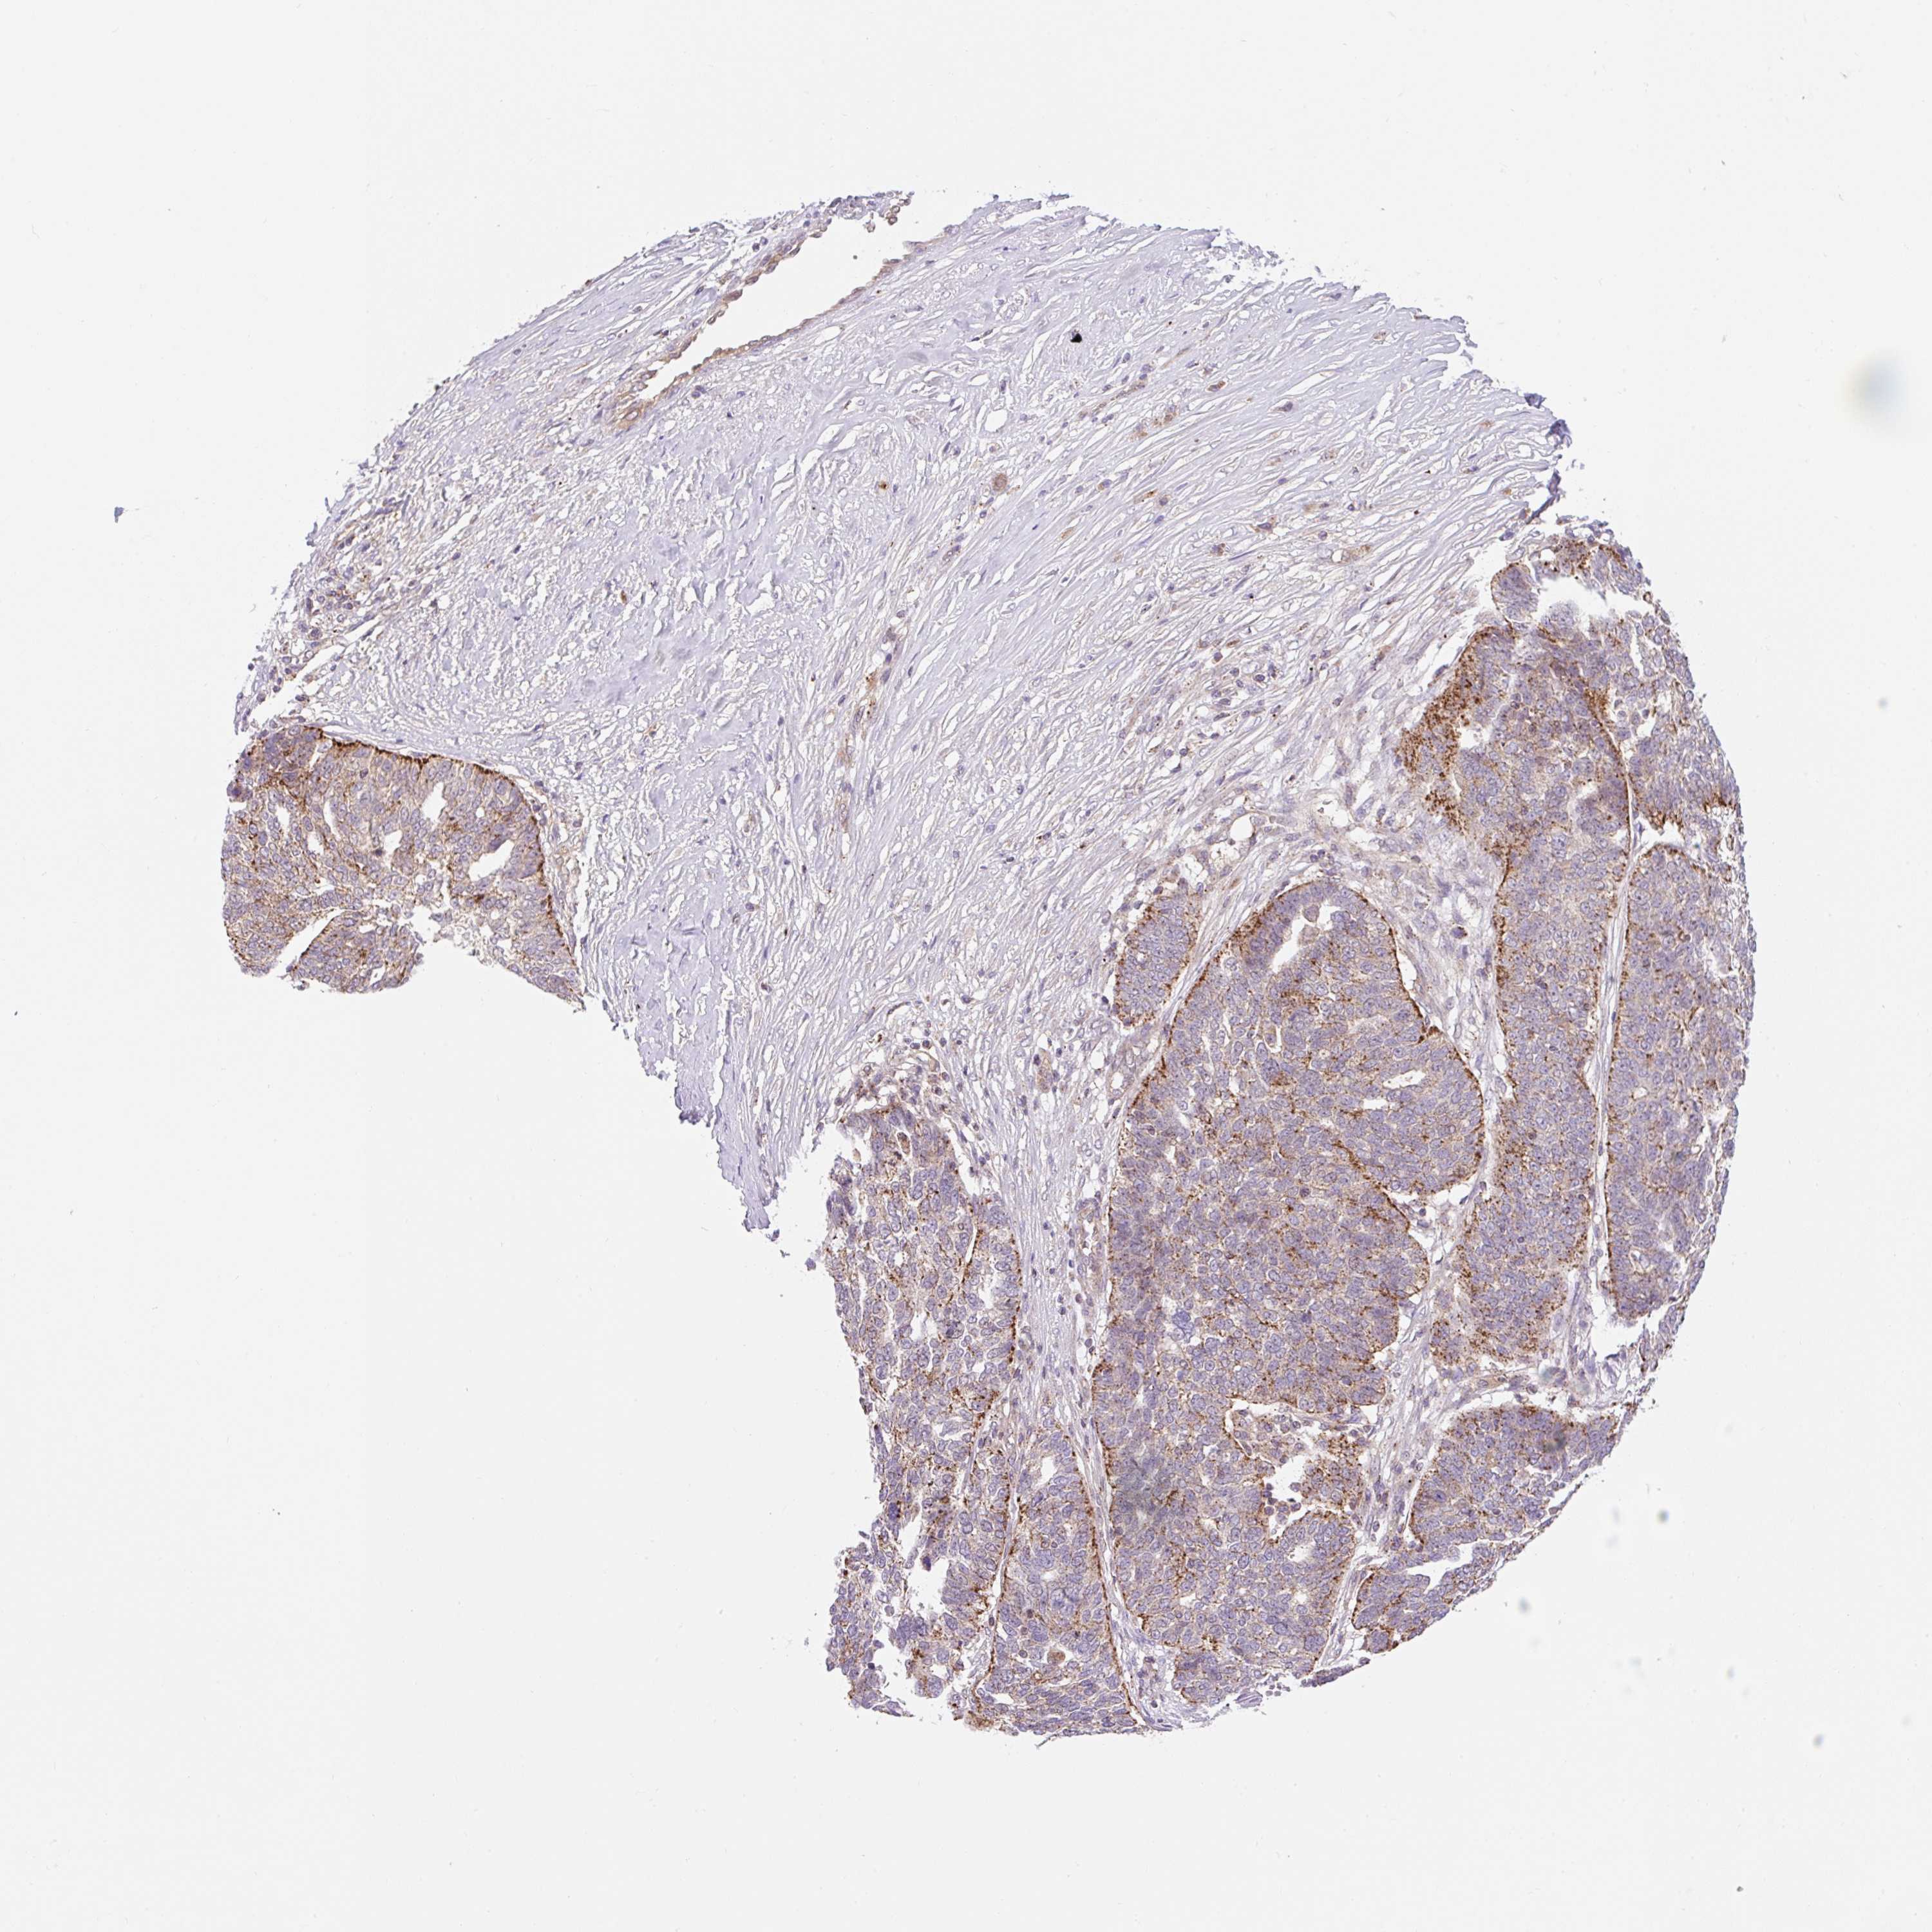

OVARIAN CANCER - Protein expressioni

A mouse-over function shows sample information and annotation data. Click on an image to view it in a full screen mode. Samples can be filtered based on level of antibody staining by selecting one or several of the following categories: high, medium, low and not detected. The assay and annotation is described here.

Note that samples used for immunohistochemistry by the Human Protein Atlas do not correspond to samples in the TCGA dataset.

Antibody stainingi

Antibody staining in the annotated cell types in the current human tissue is reported as not detected, low, medium, or high, based on conventional immunohistochemistry profiling in selected tissues. This score is based on the combination of the staining intensity and fraction of stained cells.

Each image is clickable and will lead to virtual microscopy that enables deeper exploration of all samples and also displays staining intensity scores, fraction scores and subcellular localization as well as patient and tissue information for each sample.

Antibody CAB018751

Antibody CAB034411

Staining

Cystadenocarcinoma, serous, NOS

Carcinoma, endometroid

Cystadenocarcinoma, mucinous, NOS

Carcinoma, NOS